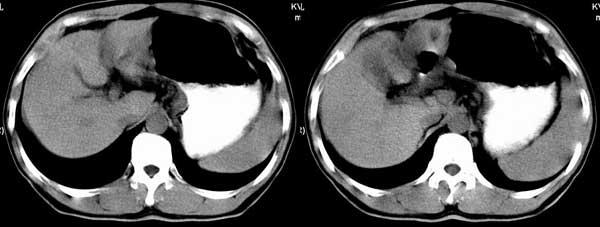

以下是引用听蝉观竹在2005-2-15 23:30:28的发言:[br]胃窦癌。[br]建议做胃镜检查并活检。

以下是引用大鹏在2005-2-16 16:14:44的发言:[br]我院用俯卧位显示胃窦部效果很好.[em4][emb26]